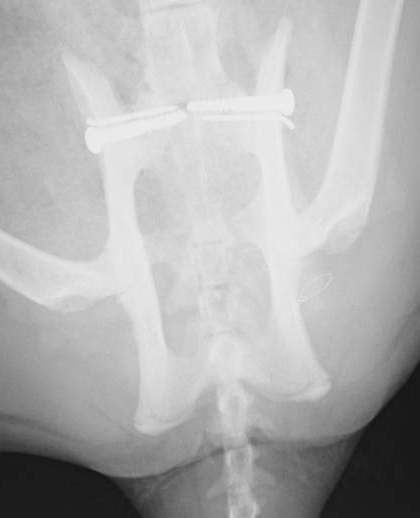

X 線を見せていただいたところ、骨盤の仙腸関節が左右で脱臼していることが判明、不幸中の幸いでしょうか、ほかの骨折は見当たりませんでした。数日間体調を確認してから、手術を行いました。腰の左右2ヶ所から整復した骨を無事留めることができました。仙骨というしっぽの付け根に当たる骨(中に太い神経が走っています)を、骨盤に左右からスクリューで留めることは、本来難しい手技ですが、今回はきれいに入れることができました。仙骨付近は、神経の分岐部が多くあるため、その後排尿障害や後枝麻痺など後遺症が残ることもあります。

数日して自宅安静で退院となりましたが、その際診察台からキャリーケースに普通に歩いていったのをみて、安心しました。今後は、室内で飼育していただけることになったので、こういった怪我もしなくなると思います。自宅のトイレでおしっこもできました。よかったね、ダヤンちゃん!

来院時、痛くてかなり鳴いていました・・・仙骨と骨盤が外れています。 | 左右からスクリューとピンで留めました。かなり安定して、痛みも数日でなくなったことでしょう。 |